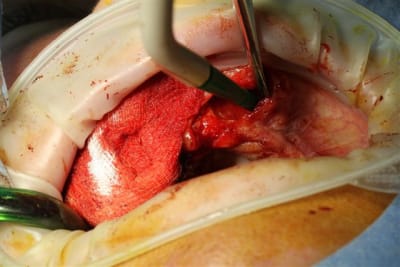

1 les séances d'ostéotension avait transformées le site, en quantité et qualité, j'aurais presque pu faire de l'expansion,mais les greffons étaient prêts, alors.

Comme prévu incision palatine à gauche , lambeau et après curetage de la zone 22, pose du greffon, ajustage parfait, vissage facile puisque les trous étaient faits (ainsi qu'une petite pièce de réparation pour la partie que j'avais abimé lors de la préparation

et du greffon)

et à droite, tunnelisation super simple.

merci Posit la reconstruction 3D était parfaitement fidèle et merci Raphaël Bardonnet (Biobank) le produit livré était parfait.

Seul Bémol, vidéo niet, le perchiste n'étant pas là nous avons loupé le vissage du premier greffon...et photos bof, D57 n'ayant pas pu se déplacer.

2, 3 photos quand même.

Bravo! succès à suivre... les photos de 2X2 imbibé de sang...moins spectaculaire...mais le but est atteint 2 blocs allogènes bien fixés en place avec incision minime...on voit quand même les points au niveau de l'ouverture pour la vis au niveau de la tunélisation c'est bien...Bravo maître... J'aimerais en savois plus sur le protocole des ostéotenseurs... Vous vous en servez en pré-op pour l'expansion?